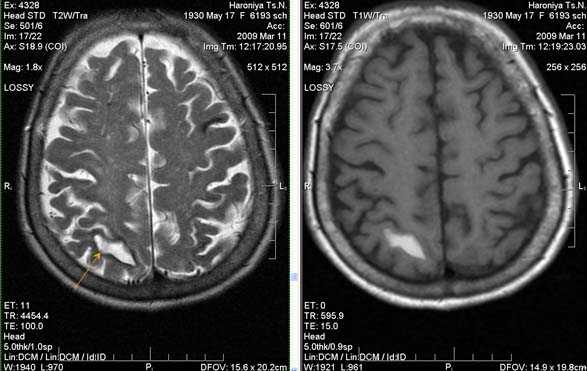

Внутримозговая гематома правой теменной доли. Граница поздней подострой и ранней хронической стадии. В Т2-ВИ виден ободок гемосидерина (стрелка).

Хочется подчеркнуть возможность МРТ в выявлении последствий геморрагического поражения - остается хорошо дифференцируемый по Т2 ободок гемосидерина, недоступный для визуализации при других методах нейровизуализации.

Стрелками показан ободок гемосидерина по периферии постишемической кисты.